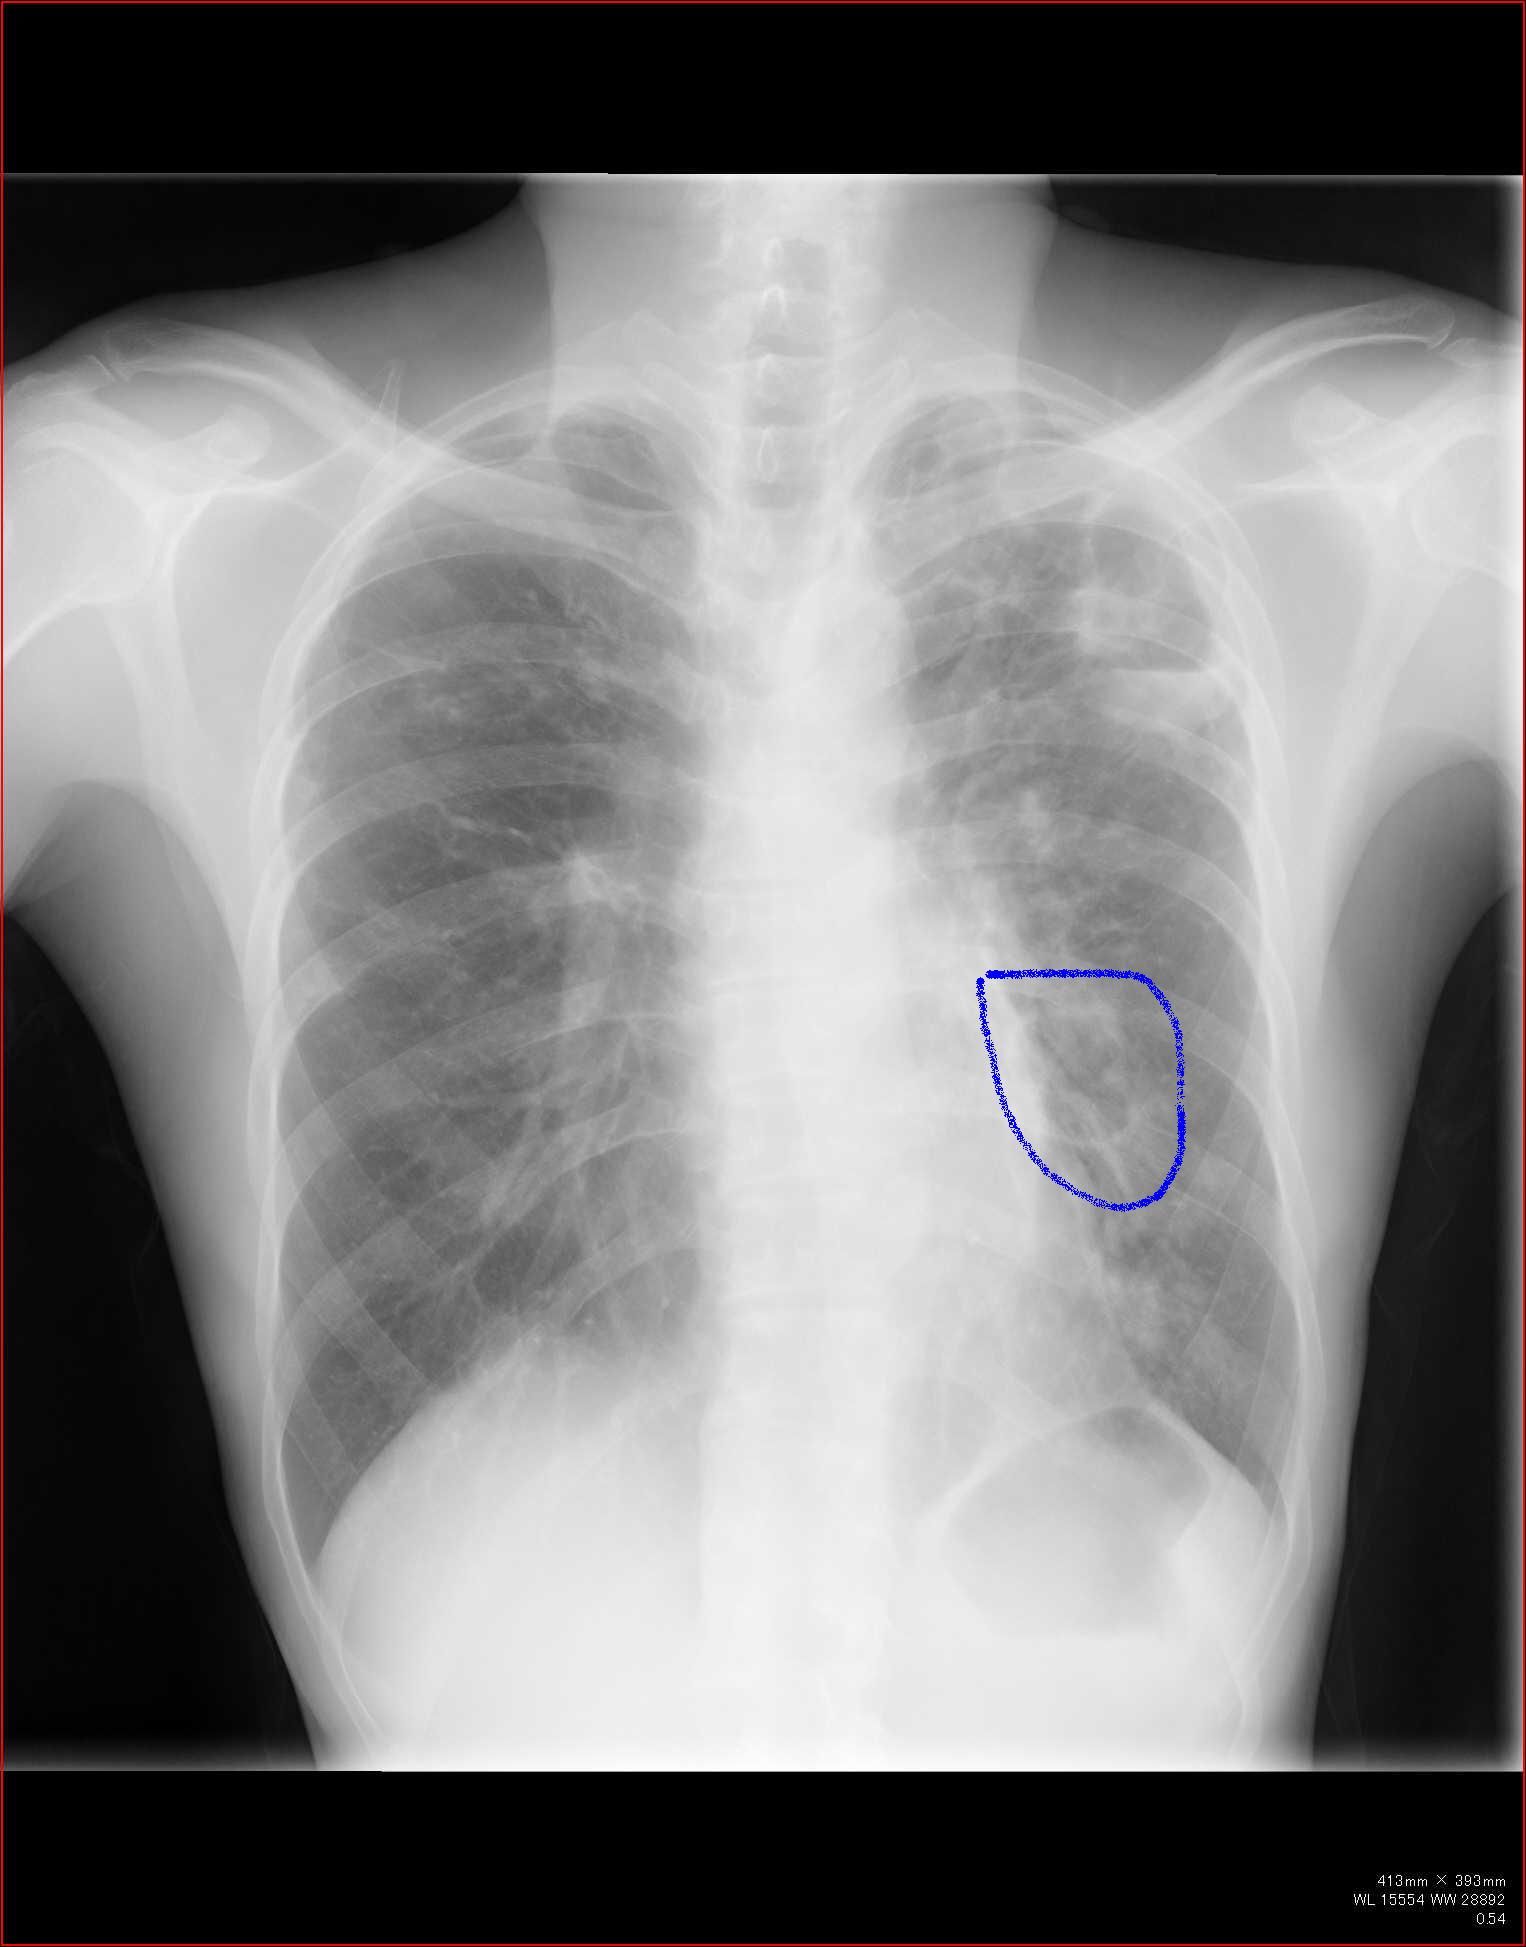

こちらを見て下さい。

わかりにくいかもしれませんが、このあたり。

気管が追いにくい、無くなっているようにも見えます。

気管狭窄ですね。こういう所見もレントゲンで捉えることができるのです。